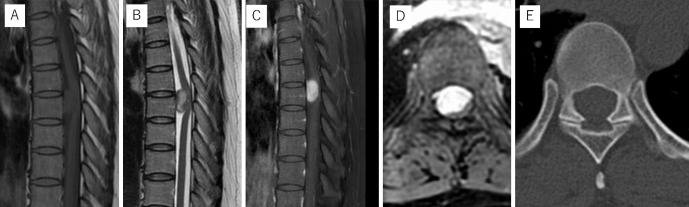

A Case of an Iatrogenic Pseudomeningocele after Thoracic Spinal Cord Tumor Surgery with a Long-Term Follow-Up.

一例胸椎脊髓肿瘤手术后的先天性假性脊髓膜膨出症及长期随访。